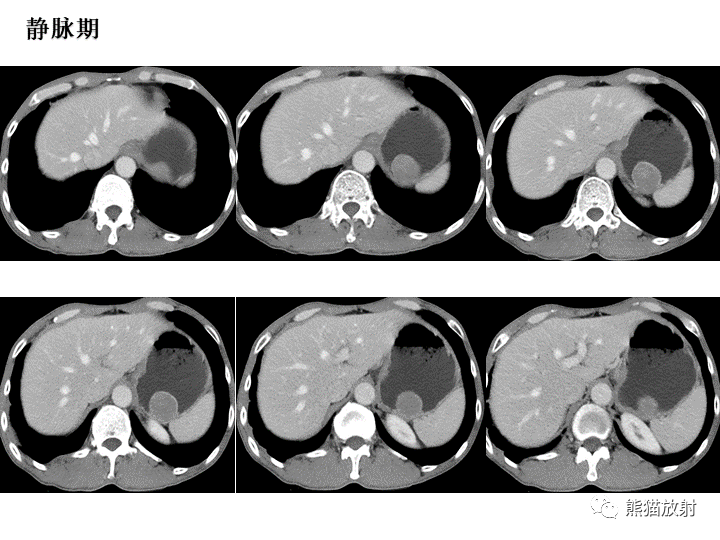

【病例】胃间质瘤VS神经鞘瘤-2